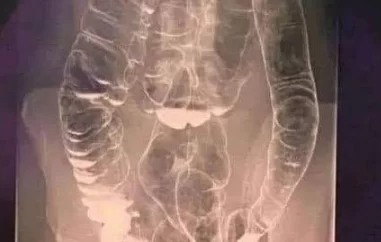

Cólon Saturado: Quando o Corpo Dá Sinais de Alerta

Você sabia que o cólon, parte vital do seu sistema digestivo, pode dar sinais claros de que está sobrecarregado? Em um mundo onde a alimentação ultraprocessada, o estresse crônico e o sedentarismo se tornaram rotina, o acúmulo de toxinas no intestino pode comprometer sua saúde intestinal e, consequentemente, sua qualidade de vida.

Os Sinais de que o Cólon Está Saturado

O corpo é inteligente e emite alertas quando algo não vai bem. Os principais sinais de um cólon saturado incluem:

Esses sintomas, quando ignorados, podem aumentar o risco de doenças inflamatórias intestinais, síndrome do intestino irritável e até câncer colorretal, um dos tipos que mais cresce entre adultos jovens, segundo estudos recentes de gastroenterologia.